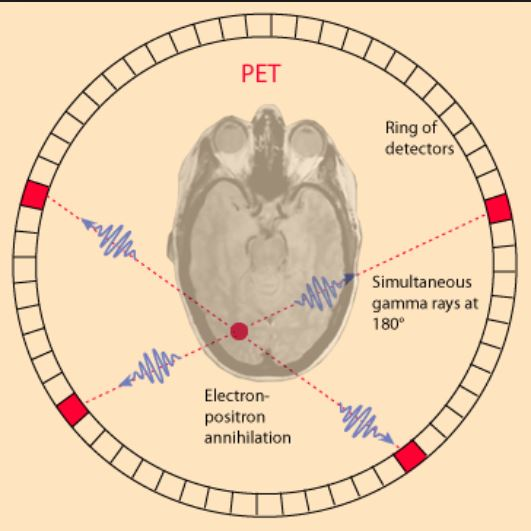

What type of energy interaction does a PET camera pick up on?

Picks up on the energy emitted from an annihilation interaction between an electron and a positron that’s lost energy – positively charged electron

How many photons are made during an annihilation reaction?

2 photons are emitted – one is equal to 511 keV

What is the total energy made when an annihilation reaction occurs?

1.02 MeV – 511 keV + 511 keV

Picks up 2 photons – the photons emitted from an annihilation reaction

When the photons from an annihilation reaction are emitted, they will travel in opposite directions of one another – makes a 180-degree line almost

What is a true coincidence?

This is the type of annihilation event that we want to occur – the detectors pick up on the energies emitted from annihilation directly opposite of each other (180°)